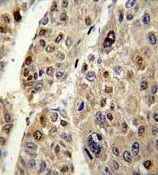

IHC-P analysis of human hepatocarcinoma using GTX81758 Antithrombin III antibody, C-term.